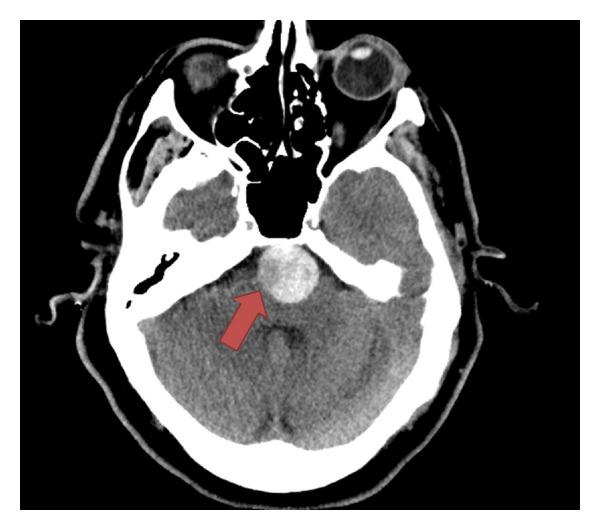

Large basilar aneurysm with posterior inferior cerebellar artery stroke and consequential fatal subarachnoid hemorrhage.

Basilar artery aneurysm presenting a stroke is rare, and we present a case of this along with a discussion of the management options available.

以卒中为表现的基底动脉动脉瘤很罕见,我们在此报告一例,并讨论现有的治疗选择。